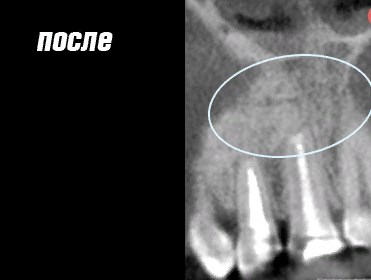

Работы врача

Фото ДО

Фото ПОСЛЕ

Наведите для просмотра

Лечение каналов